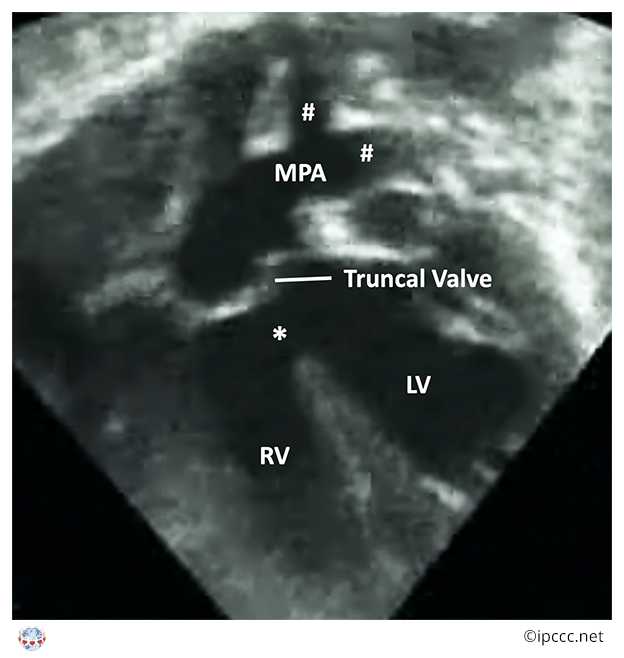

A congenital cardiovascular malformation in which a common arterial trunk is associated with an unobstructed aortic arch and both pulmonary arteries arise from the common arterial trunk.

This category includes Collett and Edwards truncus arteriosus types I, II, III and Van Praagh truncus arteriosus types 1, 2.

Echocardiogram